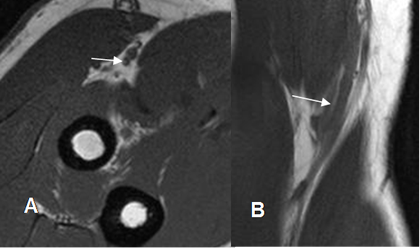

Los ligamentos son engrosamientos fibrosos de la cápsula y se valoración requiere de imágenes coronales oblicuas y axiales de RM. (1). (Fig 17, 18, 19, 20 y 21). La prueba de elección para su valoración, es la ArtroRM guiada con fluoroscopia. (9).

Fig 21. Ligamento colateral ulnar lateral normal.

RM coronal en T1.